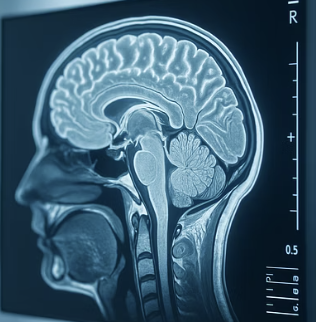

우선 이 병이 왜 생기는지부터 아주 쉽게 이해해야 합니다. 우리 뇌는 세상에서 가장 정교하고 예민한 컴퓨터와 같습니다. 이 컴퓨터가 잘 작동하려면 깨끗한 에너지(영양분)가 계속 공급되어야 하죠. 하지만 알코올은 이 컴퓨터에 계속해서 ‘독성 물질’을 쏟아붓는 것과 같습니다. 뇌세포를 직접 파괴하기도 하고, 혈관을 손상시켜 뇌로 가는 영양 공급을 막아버리기도 합니다.

특히 술은 우리 뇌가 꼭 필요로 하는 필수 영양소, 그중에서도 ‘비타민 B1(티아민)’을 우리 몸에서 빼앗아가는 아주 나쁜 도둑입니다. 이 비타민이 부족해지면 뇌는 기억을 저장하고 꺼내 쓰는 데 심각한 고장을 일으키게 되는데, 이것이 바로 알코올성 치매의 핵심적인 원인 중 하나입니다. 따라서 이 문제를 해결하기 위한 첫걸음은, 당연하게도 뇌에 독을 공급하는 행위를 즉시 멈추는 것입니다.

알코올성 치매가 다른 치매와 구별되는 가장 중요한 희망적인 특징은 바로 ‘가역성’, 즉 되돌릴 수 있는 가능성이 있다는 점입니다. 뇌세포가 아직 완전히 죽지 않고, 독성 물질 때문에 기능이 잠시 멈춰있거나 기절해 있는 상태라면, 그 원인 물질인 술만 차단해도 뇌는 스스로 회복할 기회를 얻게 됩니다.

그렇다면 술을 끊었을 때, 우리 뇌에서는 어떤 긍정적인 변화가 시작될까요? 가장 먼저, 더 이상의 뇌세포 파괴가 멈춥니다. 매일같이 쏟아지던 공격이 멈추니, 뇌는 비로소 숨을 돌리고 스스로를 치유할 시간을 갖게 되죠. 이와 동시에 부족했던 비타민 B1과 같은 필수 영양소를 적극적으로 공급해주면, 기절해 있던 뇌세포들이 서서히 깨어나기 시작합니다.